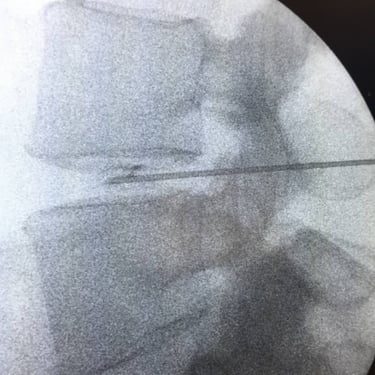

An intriguing case involved severe herniation and disc rupture between L4 and L5 vertebrae, causing intense pain. Opting out of surgery, the patient chose to try Discogel. Due to severe foraminal stenosis from the extruded disc, the Discogel injection was cautiously prolonged to one hour. Post-injection CT scan revealed effective penetration into fragmented disc components in the narrowed foraminal space.

The patient's pain gradually diminished after 4-5 weeks, and complete relief was achieved after several months.

The first image is six months post-injection, and the second image is three years post-injection."